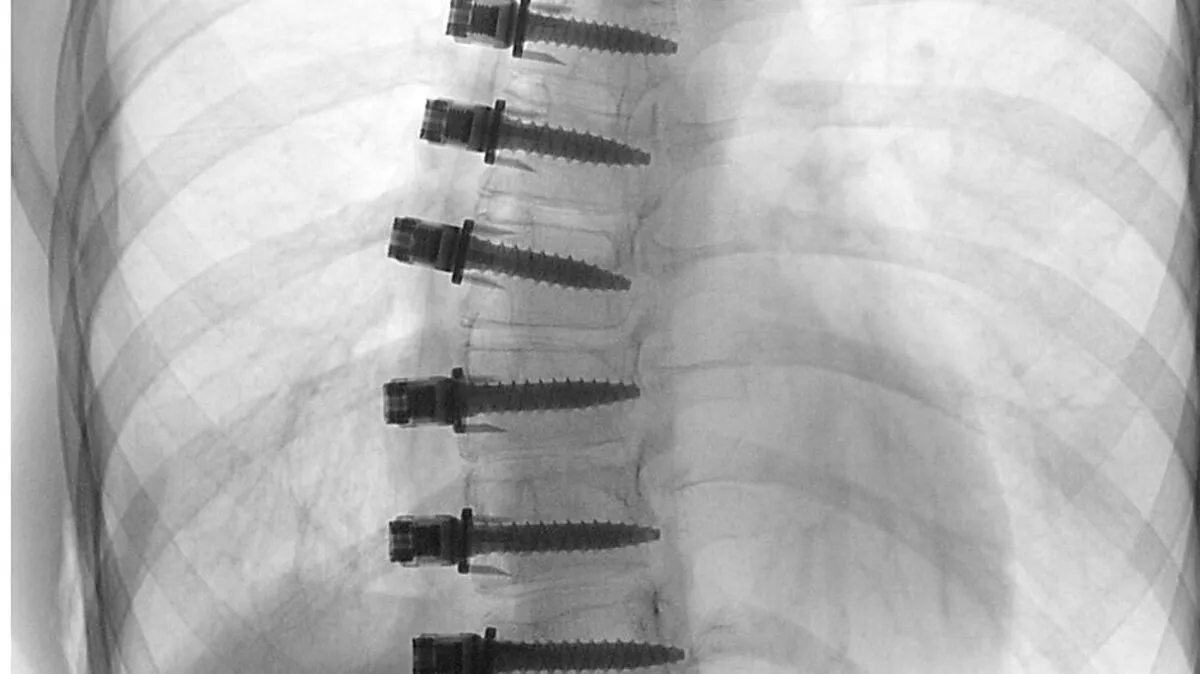

Neue Methode: Mit Seilen und Schrauben die Wirbelsäule aufrichten

Eine neue Operationsmethode bei Skoliose wurde in Graz erstmals in Österreich angewandt: wie Seile und Schrauben die Wirbelsäule aufrichten, wie es der ersten Patientin heute geht, welche Einschränkungen es gibt.